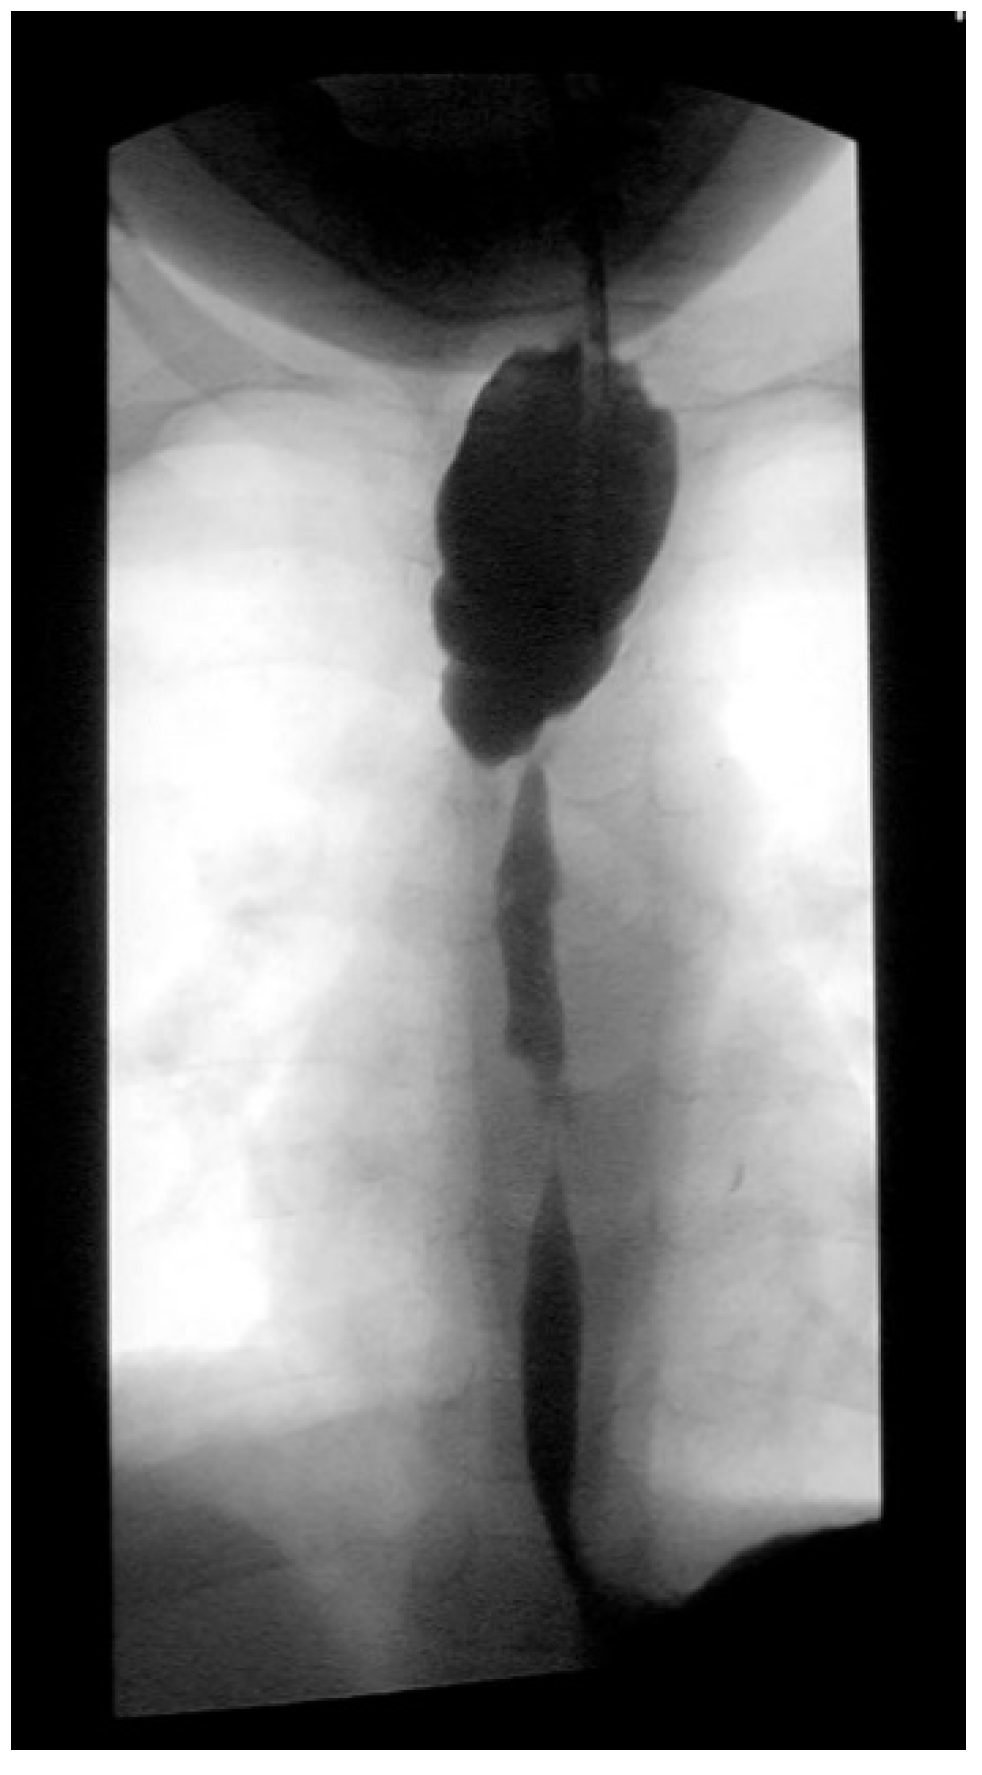

Three weeks before surgery, the children are transferred from Africa to Switzerland for the evaluation of their nutrition status, as they eventually need to be fed carefully and progressively. A thoracic X-ray and an esophagogram are performed (

Figure 2). Intubation allows an endoscopic evaluation of the grade of esophageal and pharyngial stenosis and mobility of the vocal cords (

Accidental caustic burns of the esophagus in children remain a global health problem. Conservative management by endoscopic dilatation over the first months may be possible for isolated short stenosis (one to two cm). For more than three cm, for multiple stenosis, for those with a tracheoesophageal fistula, surgical treatment is mandatory (

Figure 1). This decision has to be taken six months after the injury, as by then the lesions are totally stabilized.